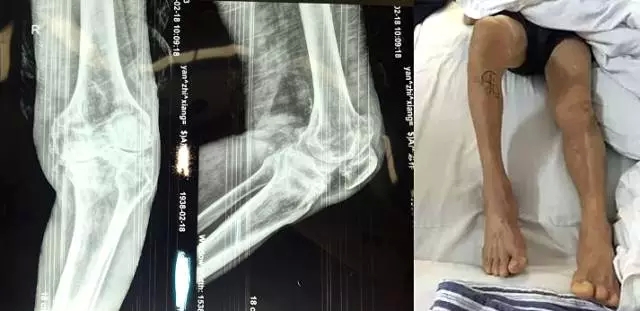

嚴(yán)老伯今年76歲,是勾山人。他右膝關(guān)節(jié)疼痛已有20多年。近五年來,嚴(yán)老伯右膝疼痛不斷加劇,右腿不僅不能自由行走,連彎曲也成了問題,最多只能彎曲50度左右。嚴(yán)老伯內(nèi)心郁悶,他說這腿把他折磨得非常痛苦,每天只能靠輪椅過日子,拖累了家人,心里十分歉疚。

“嚴(yán)老伯的右膝患有重度關(guān)節(jié)骨性關(guān)節(jié)炎,右膝內(nèi)翻畸形,如果再晚點(diǎn)來就醫(yī),他的狀況還會(huì)持續(xù)變壞。”危立軍替嚴(yán)老伯仔細(xì)檢查之后說,“鑒于他的情況,我們建議實(shí)行人工膝關(guān)節(jié)表面置換術(shù)。”

2月26日,嚴(yán)老伯在廣安醫(yī)院關(guān)節(jié)科做了膝關(guān)節(jié)表面置換手術(shù),從切開到縫合結(jié)束僅花了一個(gè)半小時(shí)。手術(shù)全過程病人基本上沒有手術(shù)后切口疼痛感,出血量不到150ml。術(shù)后第二天,他的右腿就能伸直了。

今天上午,主治醫(yī)生危立軍巡查病房時(shí)說:“嚴(yán)老伯的手術(shù)很成功,病人是非常嚴(yán)重的屈曲攣縮并內(nèi)翻畸形,膝關(guān)節(jié)平臺(tái)內(nèi)側(cè)骨缺損很嚴(yán)重。但我們采取了目前國(guó)際上最先進(jìn)的手術(shù)方法,無痛化病房管理和快速康復(fù)理念,所以病人恢復(fù)很快。”